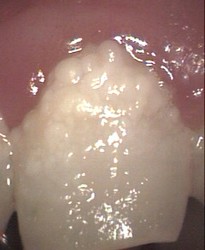

severe dysplasia(weakness) and decay laser + some moderate decay now evident

restored